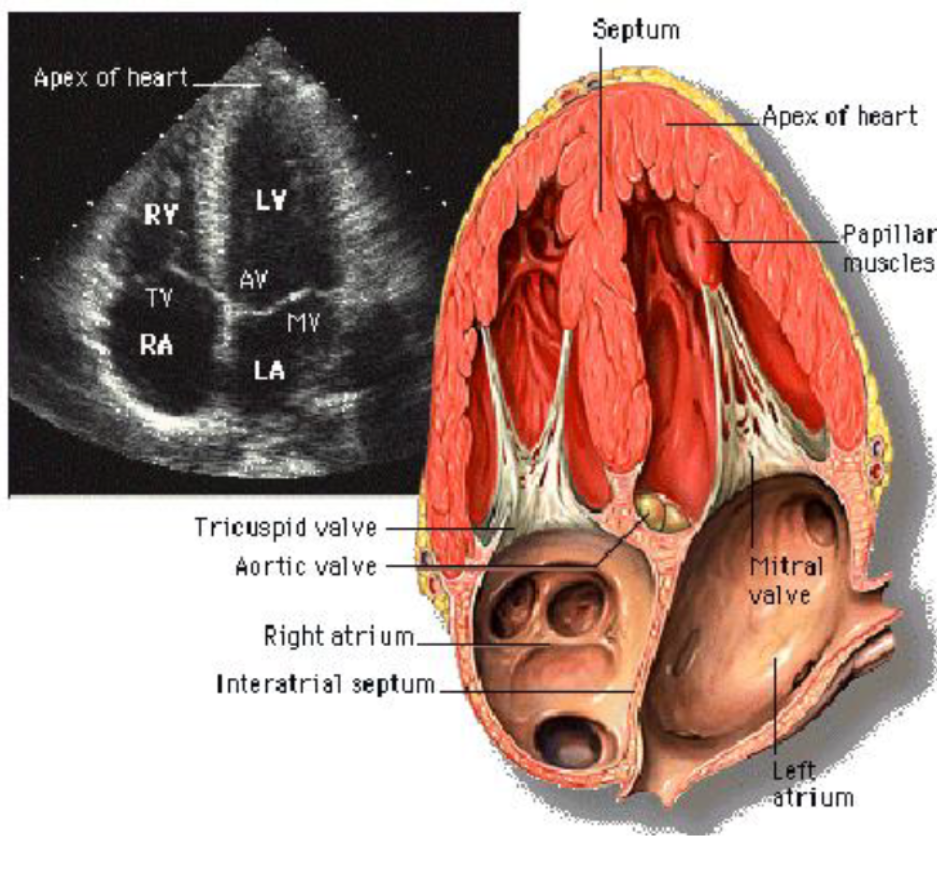

3. Apical View(5,4,3,2 chamber view)

여기서는 병원마다 pointer를 어느쪽으로 향하게 하느냐에 따라서 LV와 RV의 위치가 다른데,

구분하는 기준은 Tricuspid valve가 Mitral valve 보다 조금 높게 위치하는 것으로 알 수 있다.

심장을 아보카도 자르듯(?) 자른 단면이라고 생각하면 된다.

심첨부에 probe가 잘 가서 최대한 길게 optimal view를 잘 잡았다면,

같은 부위에서 probe를 회전시킴으로 aorta가 있는 5 chamber,

심방2개 심실2개가 보이는 4 chamber, LV & LA & aorta가 있는 3chamber,

LV 와 LA만 있는 2 chamber를 찍을 수 있다.

LV의 기능, LA크기, doppler를 통한 diastolic function, stenosis parameter,

regurgitation severity 확인 및 doppler측정 등이 가능한 view 이다.